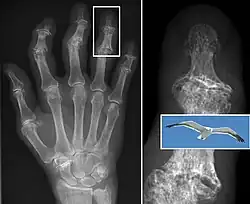

X-ray of erosive osteoarthritis of the fingers, also zooming in on two joints with the typical "gull-wing" appearance

Both primary generalized nodal osteoarthritis and erosive osteoarthritis (EOA, also called inflammatory osteoarthritis) are subsets of primary osteoarthritis. EOA is a much less common and more aggressive inflammatory form of osteoarthritis, which often affects the distal interphalangeal joints of the hand and has characteristic articular erosive changes on X-ray.[60]